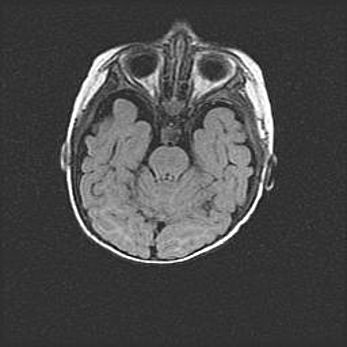

Неполная лизэнцефалия (пахигирия). Открытая гидроцефалия.

Возраст: 17 дней

Вес: 3110 г

Пол: мужской

Окружность головы: 33,5 см

Срок гестации: 35-36 недель

Лизэнцефалия—недоразвитие корковой пластинки и мозговых извилин в результате нарушения миграции нейронов коры. Поверхность мозговых полушарий гладкая. Микроскопически выявляется отсутствие нормальных слоев коры и скопление групп нейронов в подкорковом белом веществе.

Пахигирия—уменьшение числа вторичных извилин. В пораженном полушарии нервные клетки образуют толстый недифференцированный слой с неправильно расположенными нервными волокнами и группами гетеротопных клеток. Нервные клетки незрелые. Белое вещество истончено. При этом нередко аномально развит корково-спинномозговой путь.